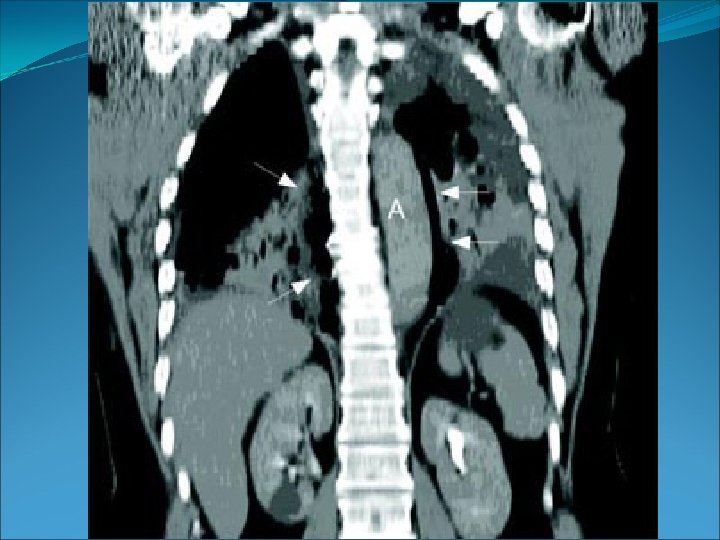

PLANOS, EJES Y MOVIMIENTOS Los planos son superficies imaginarias que dividen al cuerpo. Son 4: • Plano frontal o coronal: es un plano vertical que divide el cuerpo en dos partes, la anterior y la posterior. 6. Eje transversal. 7. 7 Eje longitudinal.

• Plano transversal, horizontal o axial: es un plano horizontal que divide el cuerpo en una parte superior y otra inferior. 6. Eje transversal.